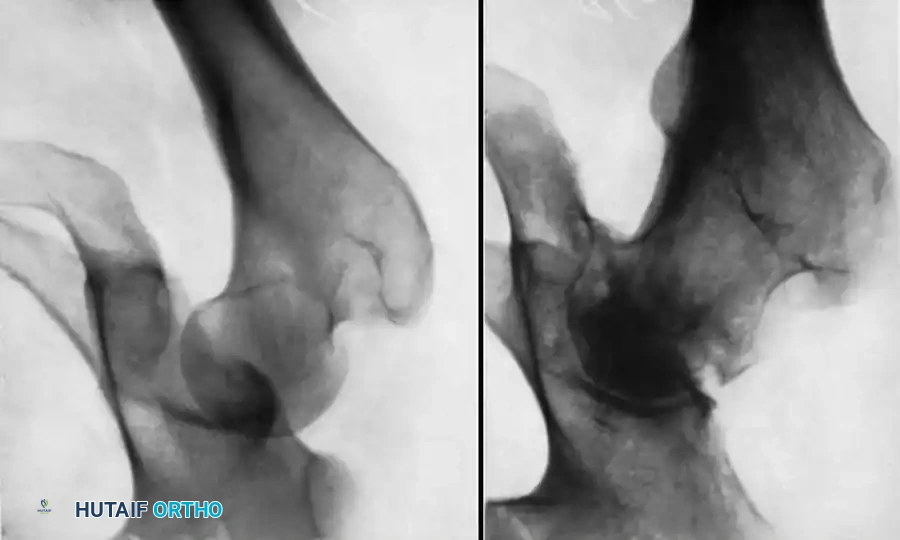

Fig. 52-44 A, Initially nondisplaced, unrecognized femoral fracture that displaced after closed intramedullary nailing of associated femoral shaft fracture. B, After closed reduction and fixation of femoral neck fracture with cannulated screws placed anterior to the femoral nail.

Fig. 52-45 Widening of the medial joint space after closed reduction indicates a nonconcentric reduction, highly suspicious for entrapped osteocartilaginous fragments or labrum.

Fig. 52-46 Axial CT scan clearly demonstrating a retained osteochondral fragment interposed between the femoral head and the acetabular dome. Operative excision is strictly indicated.

CT scan of the pelvis providing detailed visualization of the posterior wall comminution and the relationship of the femoral head to the acetabular columns.